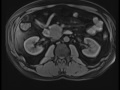

Duodenal GIST

Multiple MR images demonstrate an exophytic, likely submucosal mass arising from the second/third portions of the duodenum, representing a duodenal GI stromal tumor